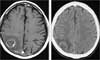

The CT images-both with contrast (A) and without contrast (B)-show a ring-enhancing shadow. In a patient with subgroup C3 HIV infection and a single, thin-walled enhancing lesion in the brain, and in whom results of Toxoplasma serology are negative, lymphoma is the most likely diagnosis.

Neuroradiological studies are usually sensitive for primary brain lymphomas but do not establish a definitive diagnosis. Characteristically, 1 or 2 lesions are visible on CT or MRI; lesions are located deep in the brain near the lateral ventricles, and they occur most often in the white matter rather than the gray matter. On CT, the lesions may enhance after administration of contrast. MRI scanning is more sensitive. However, definitive diagnosis requires brain biopsy.